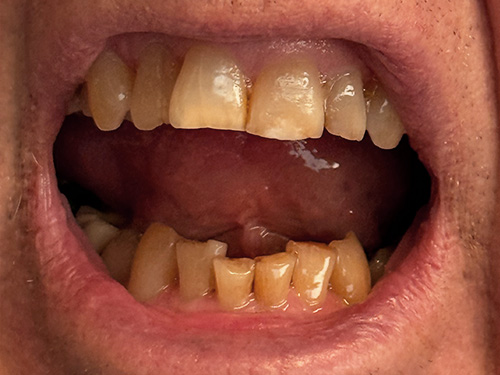

All photos shown below are real patients treated by Dr. Flex — no stock images here. Hover over each image to view the “before” photo and see the amazing results for yourself.